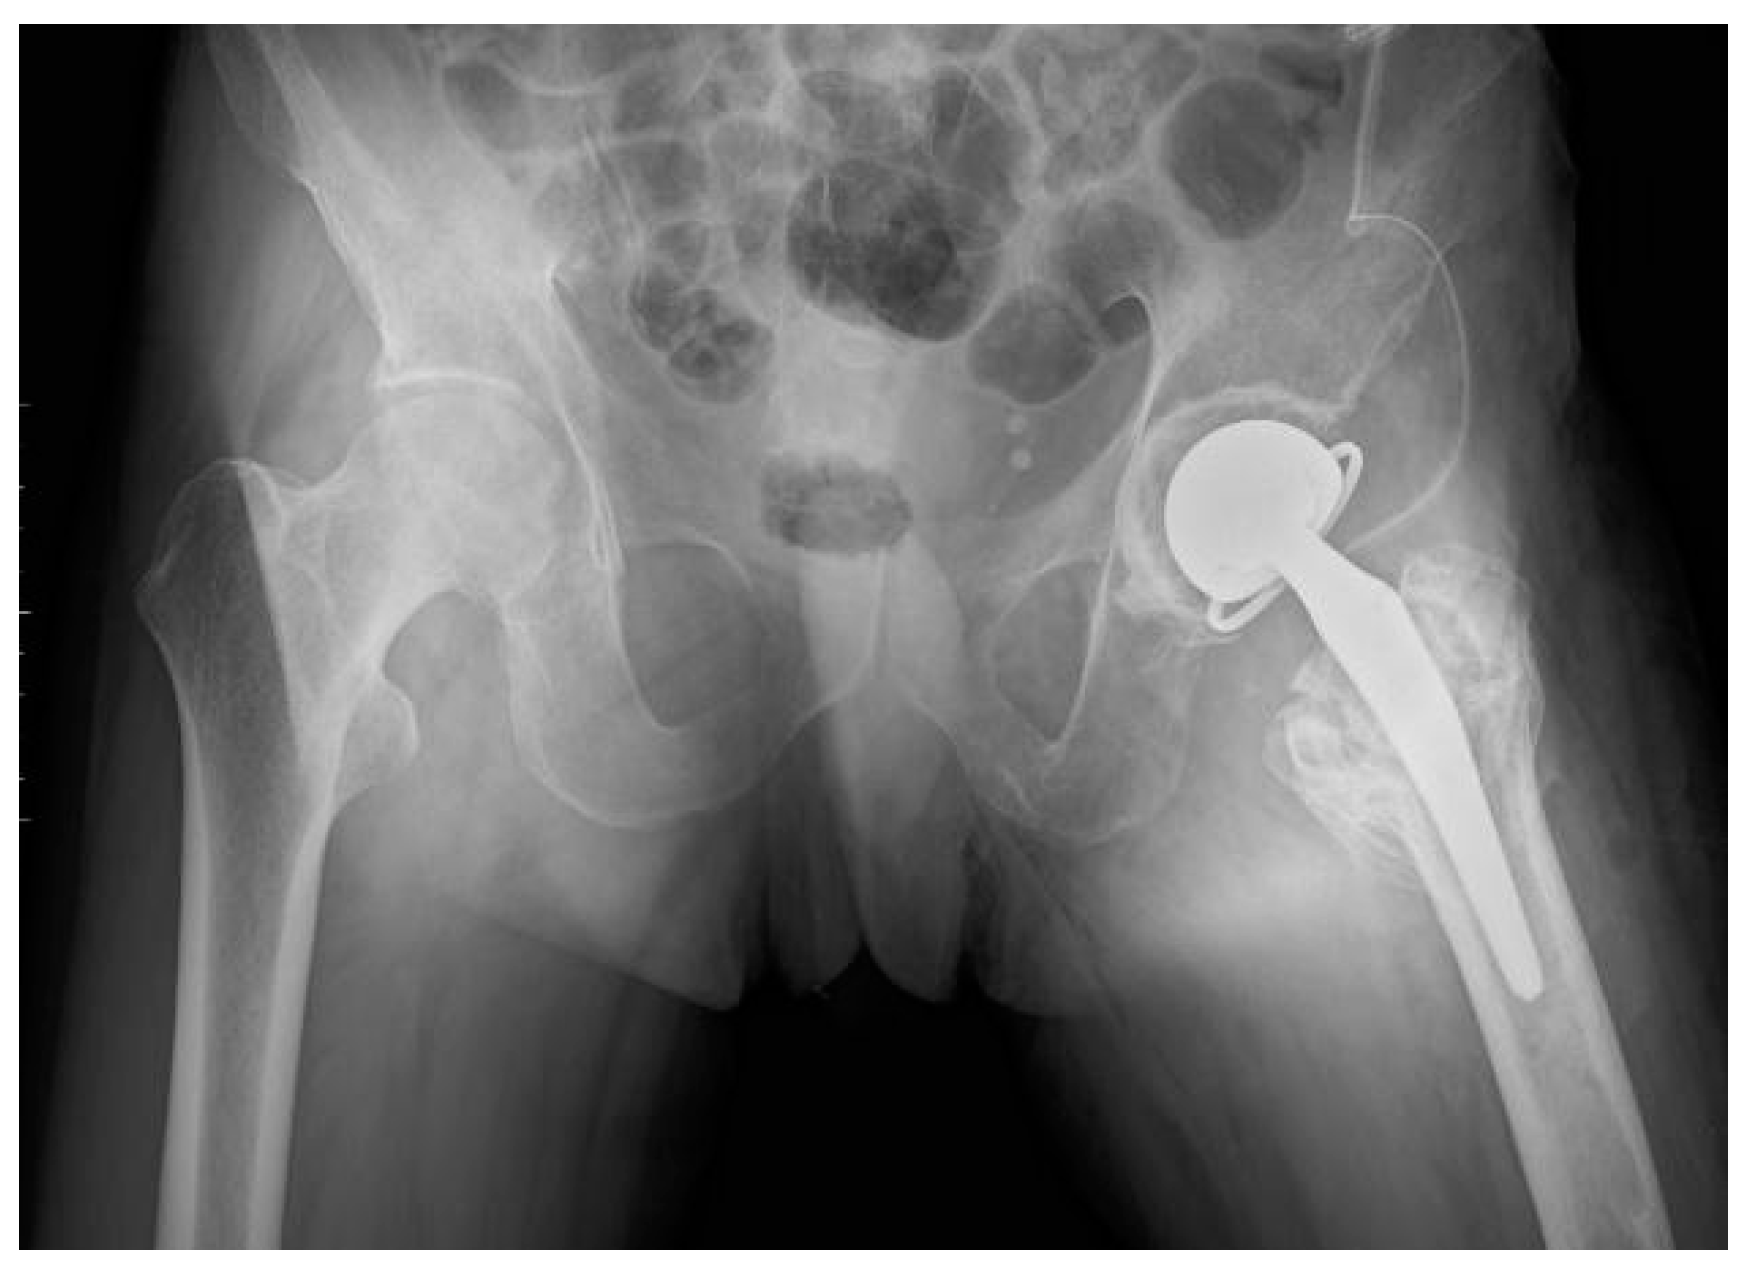

| Third Stage of Treatment—October 2023 Snap-on Prosthesoplasty with Adductor Tenotomy | ||